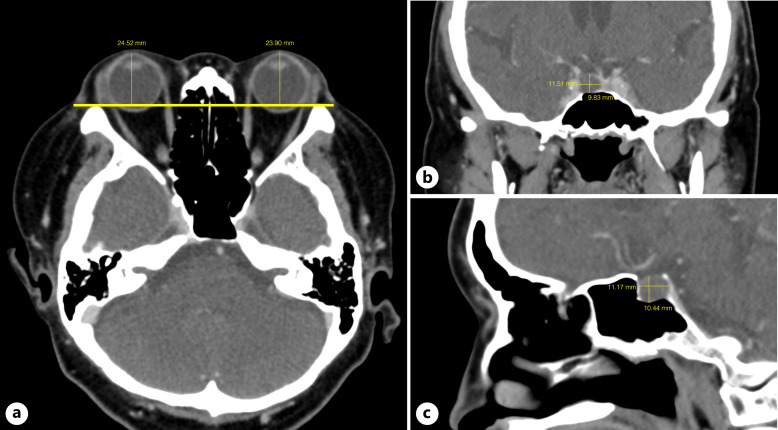

Case presentation: A 46-year-old Thai woman was referred for OHT treatment despite maximum tolerance to medication. Intraocular pressure (IOP) was 21 mm Hg (right eye) and 25 mm Hg (left eye). Visual acuity was 20/20 in both eyes. Bilateral eyelids were swollen without any palpable masses. Exophthalmometer measurements were 24 mm (right eye) and 23 mm (left eye). Extraocular muscle movements, anterior segment, gonioscopy, and dilated fundoscopic exams were normal bilaterally. Optic nerve head was unremarkable in both eyes. Optical coherence tomography showed marginal inferior thinning of the retinal nerve fiber layer and ganglion cell layer in left eye. Computerized visual field 24-2 was normal bilaterally. She was diagnosed with secondary OHT with exophthalmos in both eyes. Thyroid function and thyroid antibody tests were unremarkable. Orbital and brain computed tomography revealed exophthalmos with an increase of retrobulbar fat bilaterally and a hypodense pituitary lesion. She was diagnosed with Cushing's disease and underwent endoscopic transsphenoidal adenectomy. At 6-month postoperatively, IOP decreased to 16 mm Hg (right eye) and 17 mm Hg (left eye), without any IOP-lowering medications. Exophthalmos also improved as exophthalmometer measurements were 20 mm (right eye) and 19 mm (left eye).